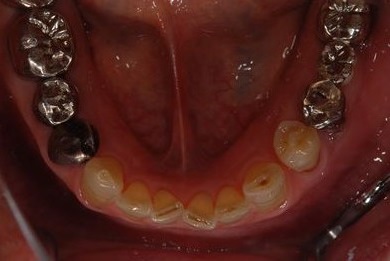

抜歯即日スピードインプラント治療+歯周外科治療

| 性別/年齢 | 男性 / 62歳 | ||||||||||||||||||||||||||||||||

| 主訴 | 左下の奥歯のブリッジがゆれて、痛みがある。 | ||||||||||||||||||||||||||||||||

| 治療方針 | 抜歯と同時にインプラント埋入を行い、治療期間を短縮する。 | ||||||||||||||||||||||||||||||||

| 治療内容 | インプラント2本(抜歯即日スピードインプラント)、ハイブリッドセラミッククラウン2本、歯周外科治療 | ||||||||||||||||||||||||||||||||

| 総治療費 | 771,960円 | ||||||||||||||||||||||||||||||||

| 治療期間 | 6ヶ月 |